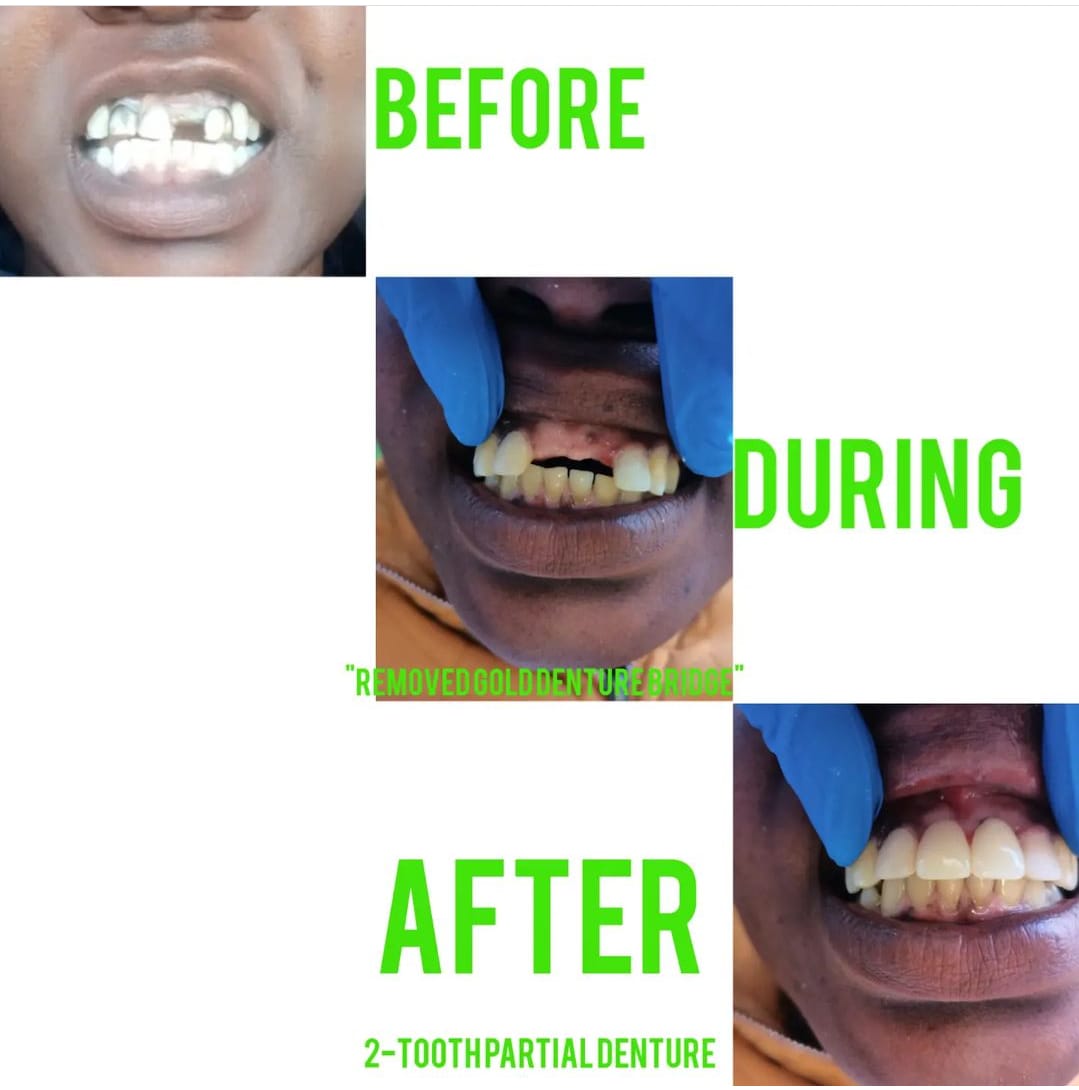

- Dentures

Our Latest Work